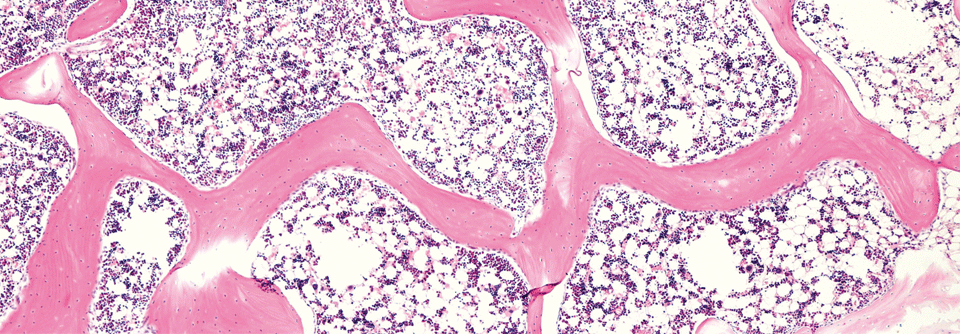

Nicht nur Verschlüsse der Koronarien sind für Betroffene höchst kritisch. Nichtobstruktive Erkrankungen wie das Takotsubo-Syndrom oder die spontane Koronararteriendissektion bringen das Herz ebenfalls in akute Lebensgefahr.